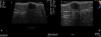

High-frequency skin ultrasound (15MHz) was performed to determine whether this was a single lesion or 2 independent lesions (Fig. 2A). B-mode ultrasound showed a well-defined, hypoechoic lesion in the subcutaneous cellular tissue; the lesion had a cystic appearance with a slightly more echogenic area on its right side. Immediately superficial to this cystic lesion, and in contact with it, was a well-defined, hypoechoic, exophytic dermal lesion. The epidermis was thickened. Doppler examination showed vessels at the periphery of the lesion, but not within it (Fig. 2B). These findings supported the clinical suspicion of a single lesion, and it was excised en bloc.

A, Skin ultrasound shows a well-defined hypoechoic lesion. On the right side of the image there is a more hyperechoic area, which could correspond to the histologic image in Figure3A. The lesion, located in the subcutaneous cellular tissue, had a cystic appearance and measured 11.24mm. It showed posterior acoustic enhancement and oblique lateral shadows. B, Echo Doppler. Blood vessels are visible at the periphery of the lesion, but not within it.

In the literature reviewed, we have found no reports that describe the skin ultrasound features of poroid hidradenoma or of lesions with a similar appearance, with a cystic component with a more superficial papular component. In our case, ultrasound and histopathology findings were concordant: a cystic lesion connected to the overlying epidermis, suggesting this was a single lesion.

The benefit of performing ultrasound in our patient was the correlation between the clinical and histopathological findings: confirmation of the clinical suspicion of a dermal lesion connected to the epidermis and of benign appearance (peripheral vascularization on ultrasound) allowed us to plan en bloc surgical excision without margins.